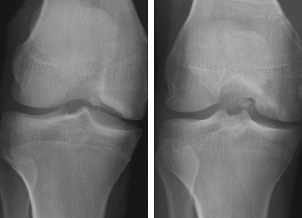

Anteroposterior and tunnel views of the right knee are shown.

Discussion: The radiographs show an osteochondral defect in the lateral aspect of the medial femoral condyle with intraarticular loose bodies (A and B). MRI of the knee, to delineate the extent of the lesion, shows an unstable, stage 4 osteochondral defect that involves the distal medial femoral condyle with at least 3 intra-articular loose bodies (C). In addition, there is small knee joint effusion with changes of mild synovitis.